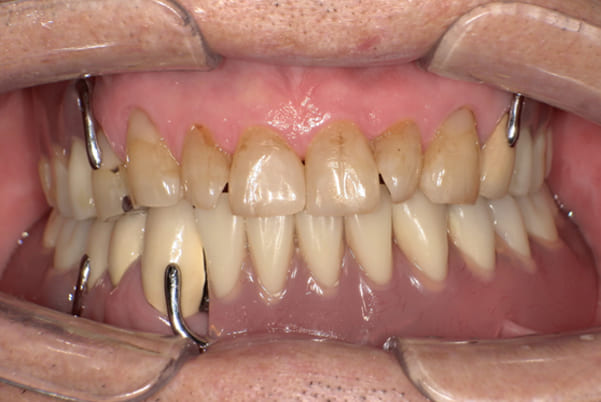

上の前歯が重度歯周病により動揺し、残せない状態のため、入れ歯も動揺がありました。

ご自身の歯に負担の少ないバネ、また見た目も改善

バネをかける歯は繋げることで強度を増し、歯への負担を軽減し、歯の寿命を長くする設計へ。

バネがかかる歯の被せ物は、歯への負担を減らし、入れ歯が動きにくいようになる形態をあらかじめ付与することで、より入れ歯の機能が高まります。

治療を行う際、被せ物や入れ歯は、別々に考えるのではなく、一口腔単位としてお口全体のことを考え最良の治療計画を立てることが歯の寿命、機能効果を向上させるため、専門医としてこのことは常に心掛けて治療を行っています。

治療前は上下奥歯の入れ歯が削れていることで、かみ合わせが低くなり唇もつむった状態でした。

かみ合わせを適切な高さに戻したことで、本来の自然な口元へ。